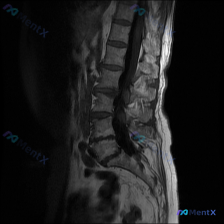

网上看到一份病例资料,用户标注提示是「脊柱侧弯」,但只给了一张腰椎MRI T2序列矢状位的图像和描述。 先把影像里的几个关键点列出来: - L4/5、L5/S1椎间盘信号明显减低(黑盘征),后缘突出,硬膜囊前缘受压 - 局部椎管矢状径变窄,黄韧带可能有肥厚 - 椎体序列生理曲度存在,未见明显楔形变或...

整理了一份影像读片的病例材料,先抛出来大家一起讨论: - 影像来源:腰椎MRI(T2序列,矢状位) - 核心影像表现: 1. L2/L3、L3/L4、L4/L5椎间盘T2低信号(黑盘征),L5/S1信号也有减低;L4/L5、L5/S1椎间隙略窄,伴椎间盘向后弥漫膨出,硬膜囊前缘受压、变形,相应节段椎...